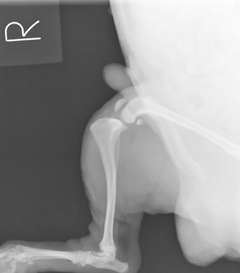

症状:3日前から急に右後足を挙上、跛行するとのことで来院。触診、レントゲン検査にて前十字靭帯断裂症が強く疑われました。

脛骨が前方に変位し、ファットパットサイン(関節炎)所見も認められます。

また、元々、膝蓋骨内方脱臼症もあり、それにより前十字靭帯に負荷がかかったものと思われました。通常は体重の軽い小型犬なら包帯などでも改善することがありますが、この症例はヨークシャーテリアですが7kg以上のかなりの肥満で、さらにクッシング症候郡も併発しており保存療法での改善は難しいと考えられました。